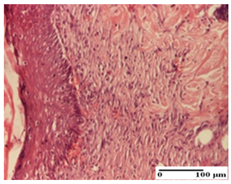

| dermal collagenization (S0, G0) | dermal collagenization—detail in polarized light microscopy (S0, G0) | dermal collagenization (S0,G0, D0) | |